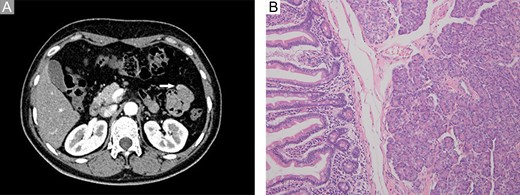

A 46-year-old woman complaining of epigastric pain for 1 month was admitted to our hospital. She denied a history of abdominal diseases or surgeries. Her physical examination results were normal. Laboratory tests, including blood routine tests as well as tests for liver and kidney function, electrolytes, pertinent serum tumor markers, were within the normal ranges except for the levels of carcinoembryonic antigen (CEA) and carbohydrate antigen 72-4 (CA72-4), which were elevated (Fig. 1). Therefore, further tests were performed. Esophagogastroduodenoscopy did not reveal anything abnormal; however, abdominal contrast-enhanced computed tomography (CT) demonstrated a persistently enhanced mass (12 mm × 8 mm in size) in the proximal jejunum (Fig. 2A). Therefore, the patient underwent an exploratory laparotomy owing to a suspicion of malignancy; a solid mass was located approximately 30 cm away from the Treitz ligament and protruded from the serosal surface. Intraoperative exploration revealed no other abnormality. Subsequently, segmental resection of the affected jejunum was performed. Surprisingly, intraoperative frozen section histopathological analysis of the resected specimen revealed pancreatic tissues; postoperative pathological examination of these pancreatic tissues confirmed the presence of jejunal ectopic pancreas containing numerous acini cells in the submucosa and muscular layer; however, malignant transformation or inflammation were not noted (Fig. 2B 200×, H&E). Thus, side-to-side anastomosis rather than extended resection was performed. More surprisingly, serum levels for the two tumor markers (CEA and CA72-4) decreased to normal levels when rechecked on the fifth day postoperatively (Fig. 1). The patient was discharged on the sixth day postoperatively, and no abnormality was noted during 6 months of follow-up.

Imaging and pathological examination findings. (A) Computed tomography scan revealed a persistently enhanced mass (approximately 12 mm × 8 mm in size) located at the proximal jejunum (white arrow). (B) Histological diagnosis revealed ectopic pancreas dominated by acini within the submucosa and muscular layer; however, no malignant transformation or other complications were observed (200×, H&E).